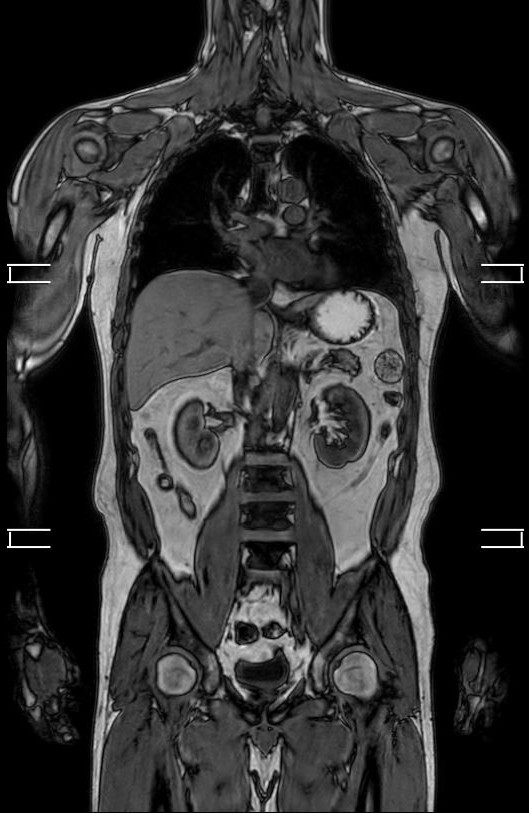

整形領域の撮影

当センターでは、体幹部のみならず四肢の撮影も行っております。膝関節、肩関節、手関節、足関節など整形領域の撮影も行っております。最新のAI技術を用いることで、より細かく描出できるようになり、靭帯損傷や骨折、筋損傷を見つけることが出来ます。

『膝関節MRI画像』